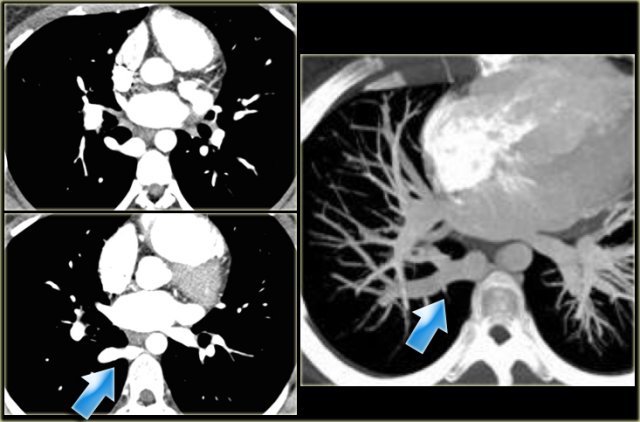

Patent Ductus Arteriosus Patent Ductus Arteriosus

Patent Ductus Arteriosus

On the left an adolescent with a murmur.

On axial image and reconstruction the patent ductus arteriosus is seen.

The ductus arteriosus is the communication between the pulmonary artery and the proximal descending aorta.

It shunts blood in utero from the right ventricle to the aorta to bypass the non-functioning lungs.

On the first day of life there is a functional closure and an anatomic closure with fibrosis in the first two weeks.

If it does not close these patients come to attention either with a murmur or later with pulmonary hypertension.

On the left a young adult with a murmur.

The cardiologists are not interested in the flow direction, but just want to confirm the diagnosis.

Notice the connection between the pulmonary artery and the descending aorta.

When the duct closes it may also calcify.

This a normal variant.